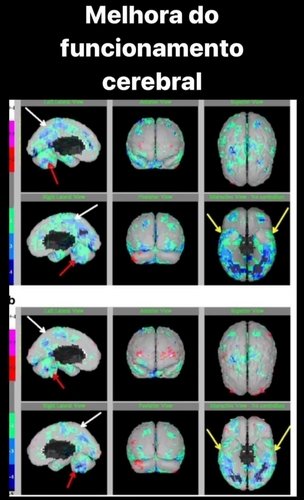

Apresento essa imagem abaixo:

Abaixo imagens dos resultados após tratamento e o orçamento de 40 sessões.

Imagens da evolução acadêmica de um autista após as sessões de câmara hiperbárica